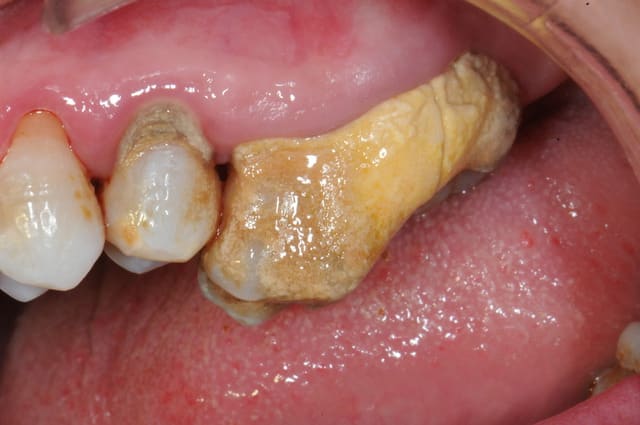

chicot29

Modeste contribution, rebasage au tartre.... Mais on peut faire mieux je n'ai pas détecté de vers à l'intérieur !